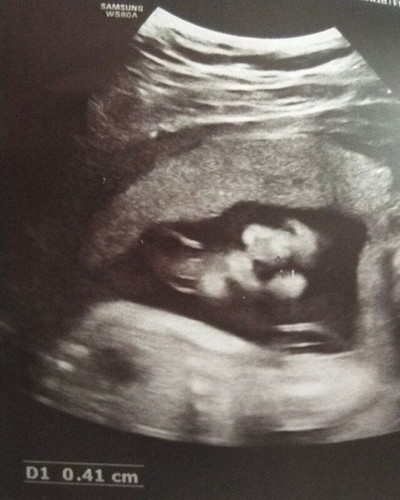

Attached photos are from my CAS and the 2last photos are from google to boost my faith na sana mali lng tlga kc wla nmn s lahi nmin ni hubby and 2weeks p lng sya s tummy alaga na s riseta kc alam q agad n buntis ako. May mga nabasa dn ako dito na nakaexperience dn ng false positive cleft lip kc matambok pisngi ni baby/ malikot habang iniiscan/dahil s shadow/angle or dhil s ambilical cord etc. . . NagpaCAS ako kc mag 7mos n sya ,nhihiya p ipakita ang gender and we're planning to celebrate this dec for a gender reveal or baby shower. Ako tlga ang nag ask s OB ko if may alam sya na nag 3D OR 4D Ultrasound para makita q dn face ni baby ko. Nirefer nya ako and bnigyan nmn nya agad aq ng request nung nagpacheck up aq s knya since 26wks nmn na si baby pero pagdating namin dun, 2d lng pla ung available s nirefer nya. Then eto n nga.. Nagpa CAS ako.Gender agad pinakita sakin and Ob ko dw mageexplain sakin ng result pero bnigyan ako ng briefing ng nagsonography sakin na okay nmn dw si baby bukod lng s nakita nyang cleft lip. Lip lng ndi kasama ang palate. Habang sinasabi nya un nakatapat s lips ni baby ung aparato and kita ko na may cleft lip nga si baby s left lips nya. Malikot si baby and nahikab p sya nun. Syempre masaya p rr ako kc atleast healthy sya and un lng nakita s knya pero d mwwla ang lungkot kc bakit s baby ko pa. Habang sinasabi sakin at habang nakatingin aq s cleft image ni baby, ndi sya msyadong tumatatak sakin na may cleft lip sya and pra sakin mukhang shadow lng sya n nagcause ng black image s bandang left nya. I expected dn kc na 3d pero 2d lng pla ung narefer sakin(black and white pa rn so prang normal ultrasound lng ung dating sakin kht mas enhance pa sya)..Matambok po pisngeh ni baby ko since 5months pa sya. Ndi sya mataba or malaking baby pra s Age nya s tummy, mana lng tlga sya sakin ng pisngi. Since sa 29 pa ako babalik s ob ko kc need q dn magpakuha ng blood sugar level kc mlaki na tummy ko, pinaread q sa friends ko n doctor ung result. Sabi nila T/C daw nkalagay , it means to consider p lng ung cleft lip so ndi p sya 100% sure. Baka ipaulit dw ng OB ko ang CAS. Pero kht ndi nya ipaulit, naghahnap n ako ng ibang hospital or clinic n may 3d and ako n lng ang magrereq na dun n lng aq magpapa ultrasound for 3d/4d. Cleft lip issue n lng ung concern ko. Pero im asking pa rin for your prayers mga mamsh.Na sana mali lng tlaga. And saNa if may cleft lip man sya sana magheal pa rn s womb..or paglabas nya ,sana cleft lip lng tlga..wag na sana pati palate nya. Super excited p rn kami pra kay baby. I know may purpose lahat .. kahit nakakalungkot, magaan pa rn ang loob nmin atleast healthy sya and thankful aq s hubby ko kc iba ung safety and assurance n pinaparamdam nya sakin mula nung naging kami at lalo n ngayong may baby kami.#firstbaby #pregnancy #1stimemom #advicepls #theasianparentph